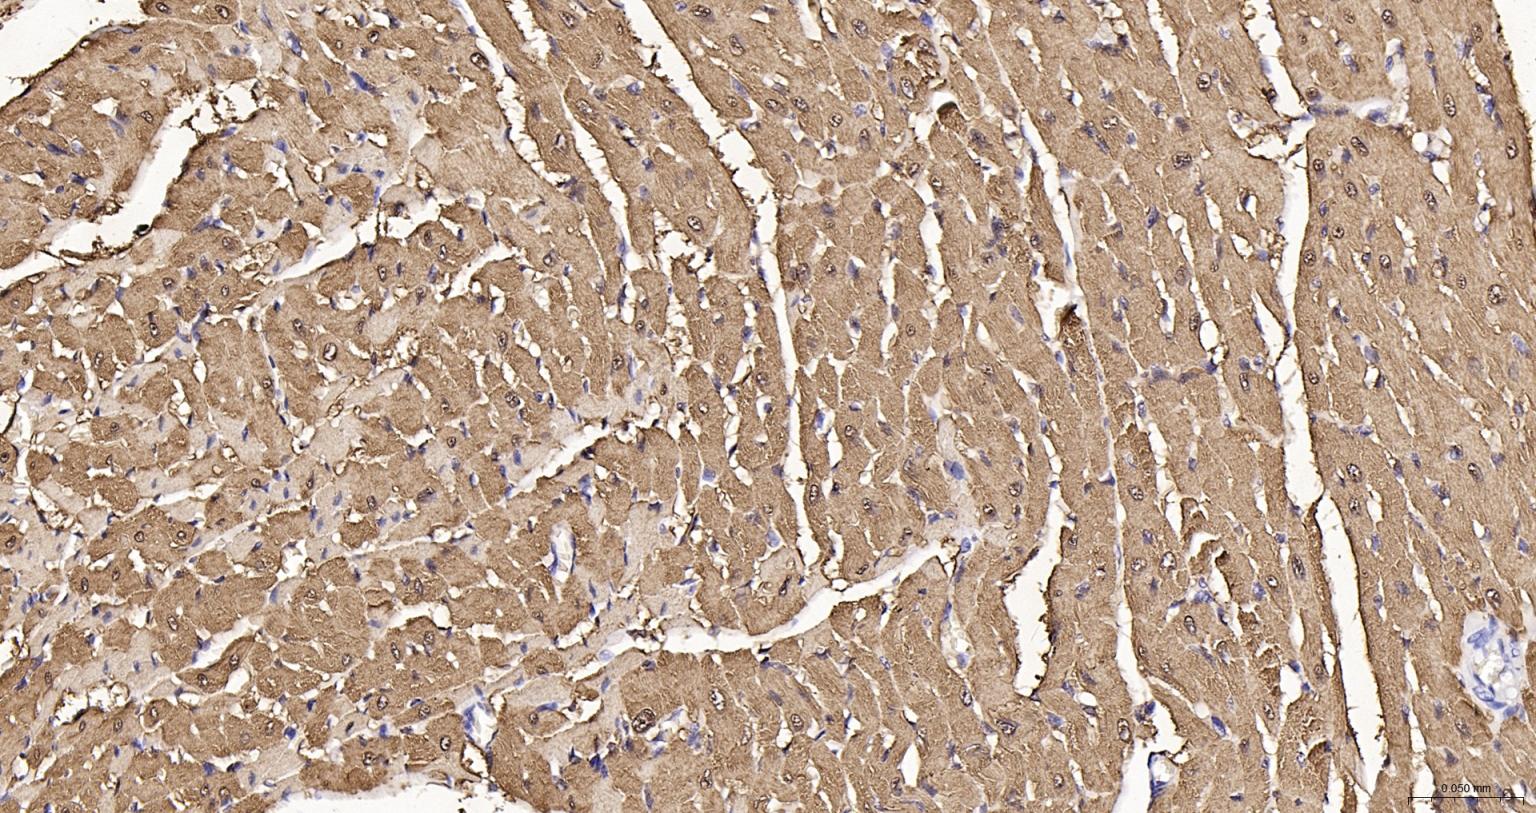

Myoglobin is a small heme containing protein responsible for the oxygen deposition in muscle tissues. Only one form of myoglobin is expressed in cardiac and skeletal muscles. Myoglobin is known as a marker of myocardial damage and it has been used for more than three decades. Nowadays it still is very commonly used in clinical practice as an early marker of AMI. It appears in patient's blood 1 to 3 hours after onset of the symptoms, reaching peak level within 8 to 12 hours. Myoglobin is not so cardiac specific as cTnI or cTnT. Because of high myoglobin concentration in skeletal muscle tissue, even minor skeletal muscle injury results in the significant increase of myoglobin concentration in blood. Thus myoglobin is used together with cTnI or cTnT in clinical practise for better specificity in AMI diagnosis.

| IHC-P | Human, Mouse, Rat | 1:200-1000 | |